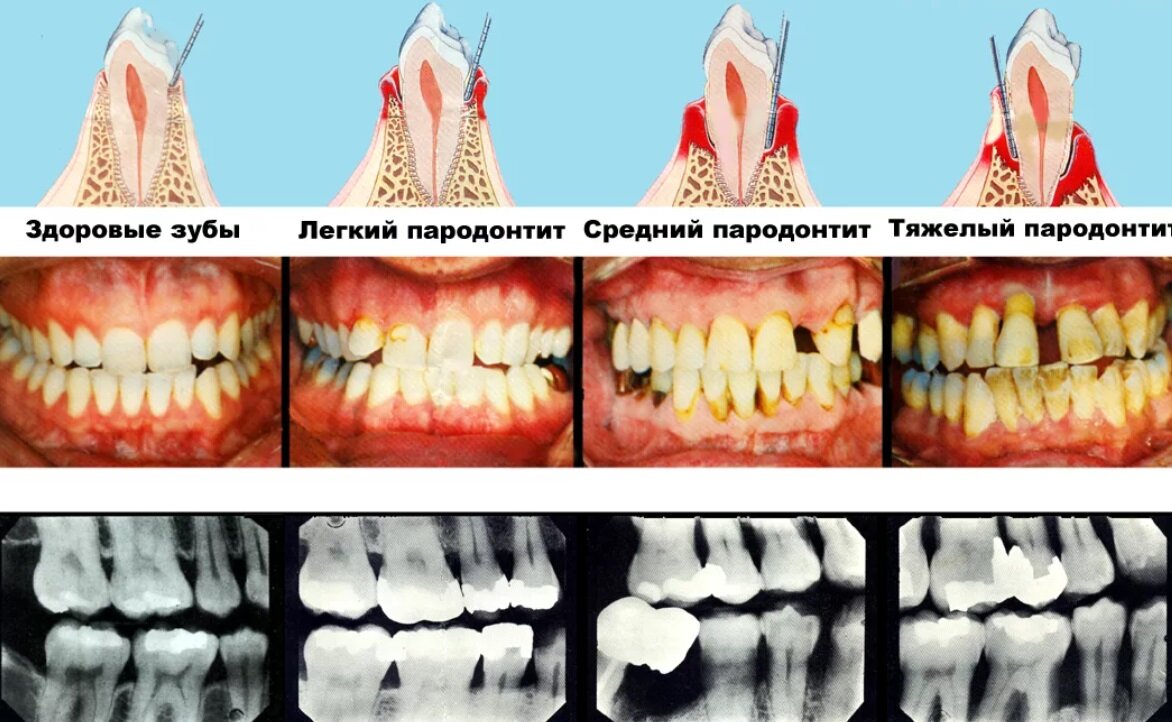

3️⃣ Злейший враг зубов - пародонт 💔

Согласно статистике, 70% населения Земли сталкиваются с заболеваниями пародонта.

Этот невидимый враг может причинить множество проблем. Следите за зубами! 🚫🦠